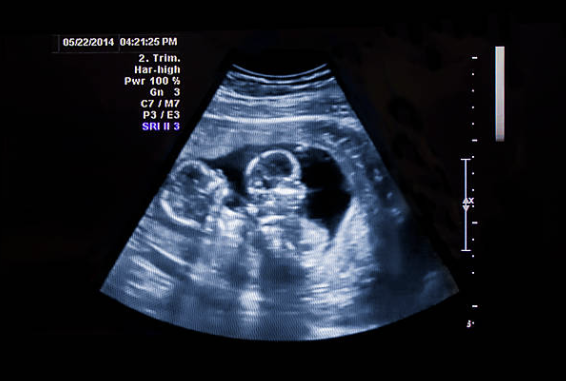

Tijdens een routinecontrole bij de dokter kreeg Angie nieuws dat haar hart opnieuw deed opspringen: ze verwachtte niet één, maar twee baby’s! Het waren twee jongens, een tweeling.